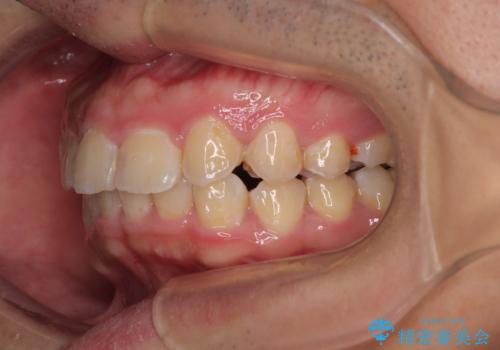

- デコボコと奥歯の咬み合わせのズレを気にして来院された患者様です。

骨格的に、下顎が右側にずれており、左側の咬み合わせに鋏状咬合などのアンバランスが生じている状態でした。

また、上顎前歯に欠損が1本あり、上下ともに前歯部に叢生が認められ、下顎前歯の大半が隠れてしまうほどの過蓋咬合も認められました。

咬合平面を平坦にしながら前歯の咬み合わせを挙上し、デコボコと鋏状咬合も改善していくこととしました。